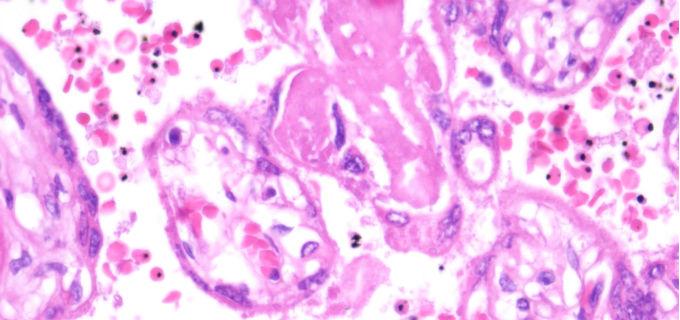

P. falciparum infection rates in pregnant women attending their first antenatal care visit can be used to estimate the burden of malaria in children living in the community, according to a study led by the Barcelona Institute of Health (ISGlobal) and the Centre for Health Research in Manhica (CISM). The study, published in Nature Communications, confirms that pregnant women are an optimal population to monitor changes in infection prevalence and to adapt control measures.

In this study, Mayor and his team measured malaria prevalence in 6,471 pregnant women attending antenatal care visits in three areas of southern Mozambique with different levels of transmission (Manhiça, Magude and Ilha Josina) and compared it with the prevalence estimated from clinical cases or from cross-sectional studies in children, in the same areas and over the same time period (2016-2019).

The analysis shows that infection rates in pregnant women closely reflect the rates in children from cross-sectional studies, especially when the parasite is detected by molecular tests (PCR). With rapid diagnostic tests, the correlation holds in low-transmission areas (Manhiça or Magude), but is lost in high-transmission areas (Ilha Josina) when multigravid women (who have had more than one pregnancy) are included. Multigravid women had a lower prevalence than the children in the community. "This is because the immunity acquired during previous pregnancies allows them to maintain low parasite densities and evade detection by rapid tests, which are less sensitive than PCR," explains Arnau Pujol, co-first author of the study with Gloria Matambisso.